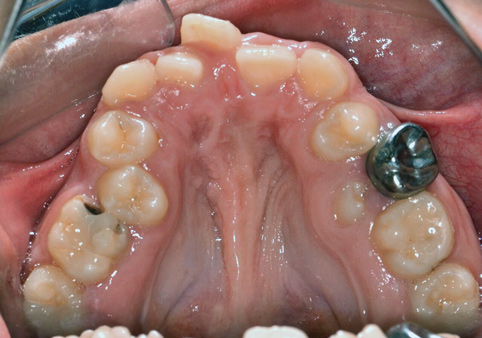

Fig 11. Severely constricted maxilla/high-vaulted palate.

Figure 11

Tongue and thumb pressures also contribute to a high-vaulted palate, which can lead to mouth breathing (Figure 11).31 Additional risks exist for infection and callus development on the thumb. Ideally, the child should quit this habit by age 4, before permanent occlusal changes develop.32 Quitting can be achieved through positive reinforcement and by offering the child comfort during thumb-sucking triggers. The use of bitterants (eg, Mavala Stop, Thum, Control-It!), which are painted on or rubbed into the thumb, is another option.33 A habit breaker appliance may also be utilized if these techniques are unsuccessful. Devices such as a palatal crib, rake, or bluegrass appliance interfere with the thumb and tongue habits and allow the bite to passively close.34 The author recommends utilizing a habit breaker appliance for 6 to 9 months and maintaining reinforcement for a few months once the habit is eliminated (Figure 12 through Figure 14).